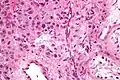

![]() Micrograph showing a cluster of Leydig cells (center of image). H&E stain. | |

Leydig cells, also known as interstitial cells of the testes and interstitial cells of Leydig, are found adjacent to the seminiferous tubules in the testicle and produce testosterone in the presence of luteinizing hormone (LH).[1][2] They are polyhedral in shape and have a large, prominent nucleus, an eosinophilic cytoplasm, and numerous lipid-filled vesicles.[3]

The mammalian Leydig cell is a polyhedral epithelioid cell with a single eccentrically located ovoid nucleus. The nucleus contains one to three prominent nucleoli and large amounts of dark-staining peripheral heterochromatin. The acidophilic cytoplasm usually contains numerous membrane-bound lipid droplets and large amounts of smooth endoplasmic reticulum (SER).[4] Besides the abundance of SER with scattered patches of rough endoplasmic reticulum, several mitochondria are also prominent within the cytoplasm. Reinke crystals have lipofuscin pigment and rod-shaped crystal-like structures 3 to 20 micrometres in diameter.[5]